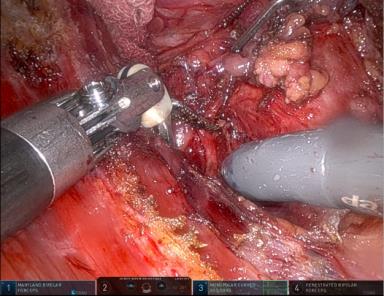

摘要:在精准医疗不断发展的背景下,机器人手术技术迅速推广,机器人甲状腺手术在国内已广泛开展,并展现出操作精细、创伤小、美容效果好等显著优势。本中心自开展该术式以来,已累计完成逾4 000例机器人甲状腺手术,积累了丰富的实践经验,尤其在手术配合与助手培养方面形成了较为成熟的体系。优秀的手术助手在确保手术顺利推进和保障患者安全方面发挥着关键作用。本文基于中心实践,系统总结了机器人甲状腺手术助手的培训要点与配合技巧,重点包括术前准备(如患者筛选、影像资料研判、喉不返神经风险评估)及术中配合(如Trocar放置、器械交接、纱布球管理与止血等)等关键环节。旨在为机器人甲状腺手术团队提供可借鉴的实用经验,助力技术规范化推广,提升团队协作水平与手术质量,为患者提供更安全、高效的医疗服务。

摘要:传统开放甲状腺手术会在颈部留下疤痕而影响美观,因此,临床上开展了多种颈外入路的腔镜甲状腺手术。由于颈部解剖特点及腔镜器械的局限,各种常规内镜手术都存在一些不足,而内镜机器人辅助甲状腺手术可以弥补上述不足。目前,内镜机器人手术系统设备贵、手术费用高,还没有普及,多数医生对此还比较陌生,随着技术发展和费用降低,内镜机器人手术应用前景广阔。本文基于本中心多年来在腔镜甲状腺手术方面的规模化实践,结合国内外机器人甲状腺手术的经验与教训,总结并提出了经双侧腋窝乳晕入路的机器人辅助腔镜甲状腺手术七步操作流程,旨在为该技术的临床推广提供参考依据。